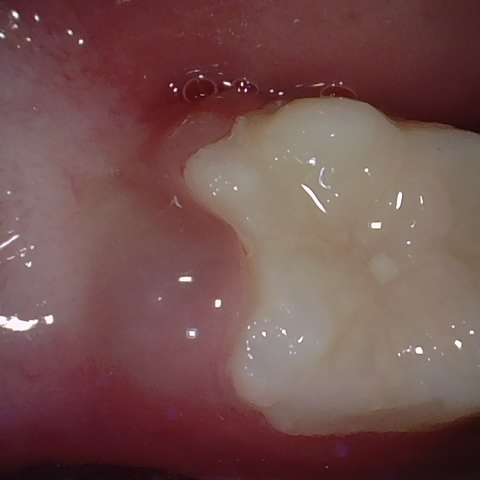

Annotated as "Good"